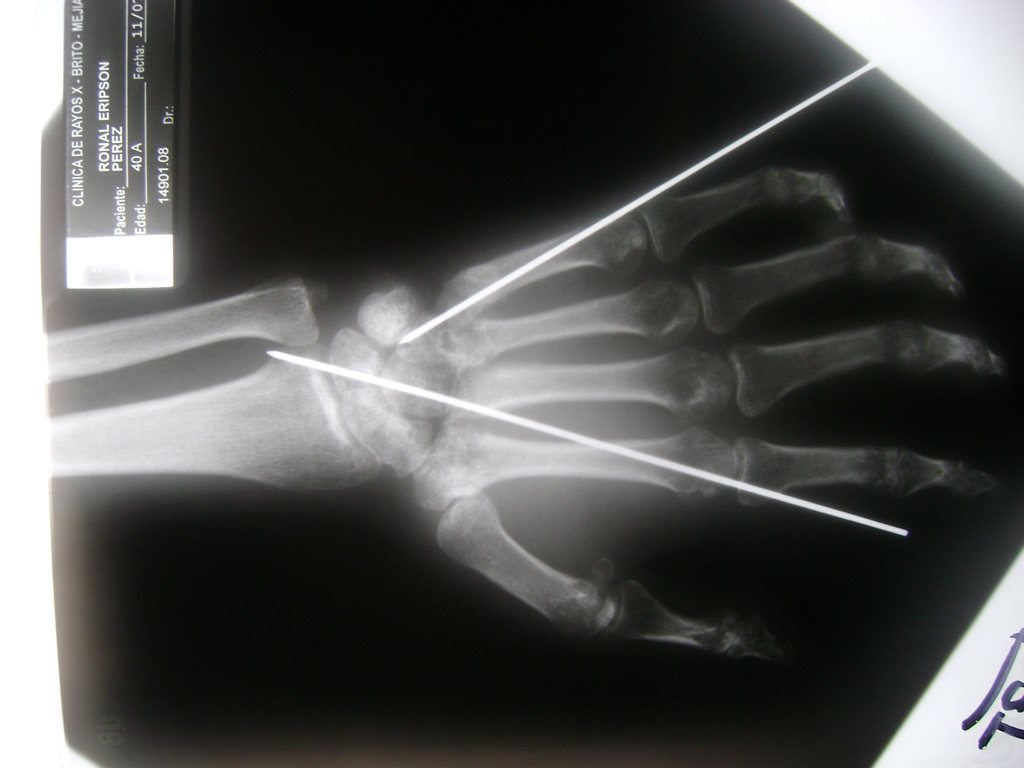

Calcaneo - Cirugías de Muñecas y Manos

Los procedimientos más comunes en cirugía de la mano son aquellos destinados a reparar traumatismos, incluyendo lesiones de tendones, nervios, vasos sanguíneos, y articulaciones; huesos fracturados; y quemaduras, cortes, y otros daños de la piel.